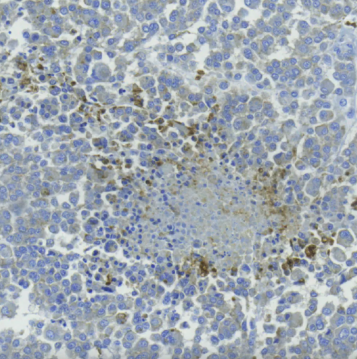

人乳腺腫瘤中辛納巴林酸的IHC檢測(cè)

人乳腺腫瘤組織的免疫組化染色顯示,在壞死區(qū)域周?chē)募?xì)胞中存在辛納巴林酸。石蠟包埋的腫瘤組織在與初級(jí)抗辛納巴林酸抗體(1:500稀釋)孵育過(guò)夜前,進(jìn)行了pH=6的抗原修復(fù)。加入聚合物偶聯(lián)的二抗,并使用DAB揭示免疫染色。